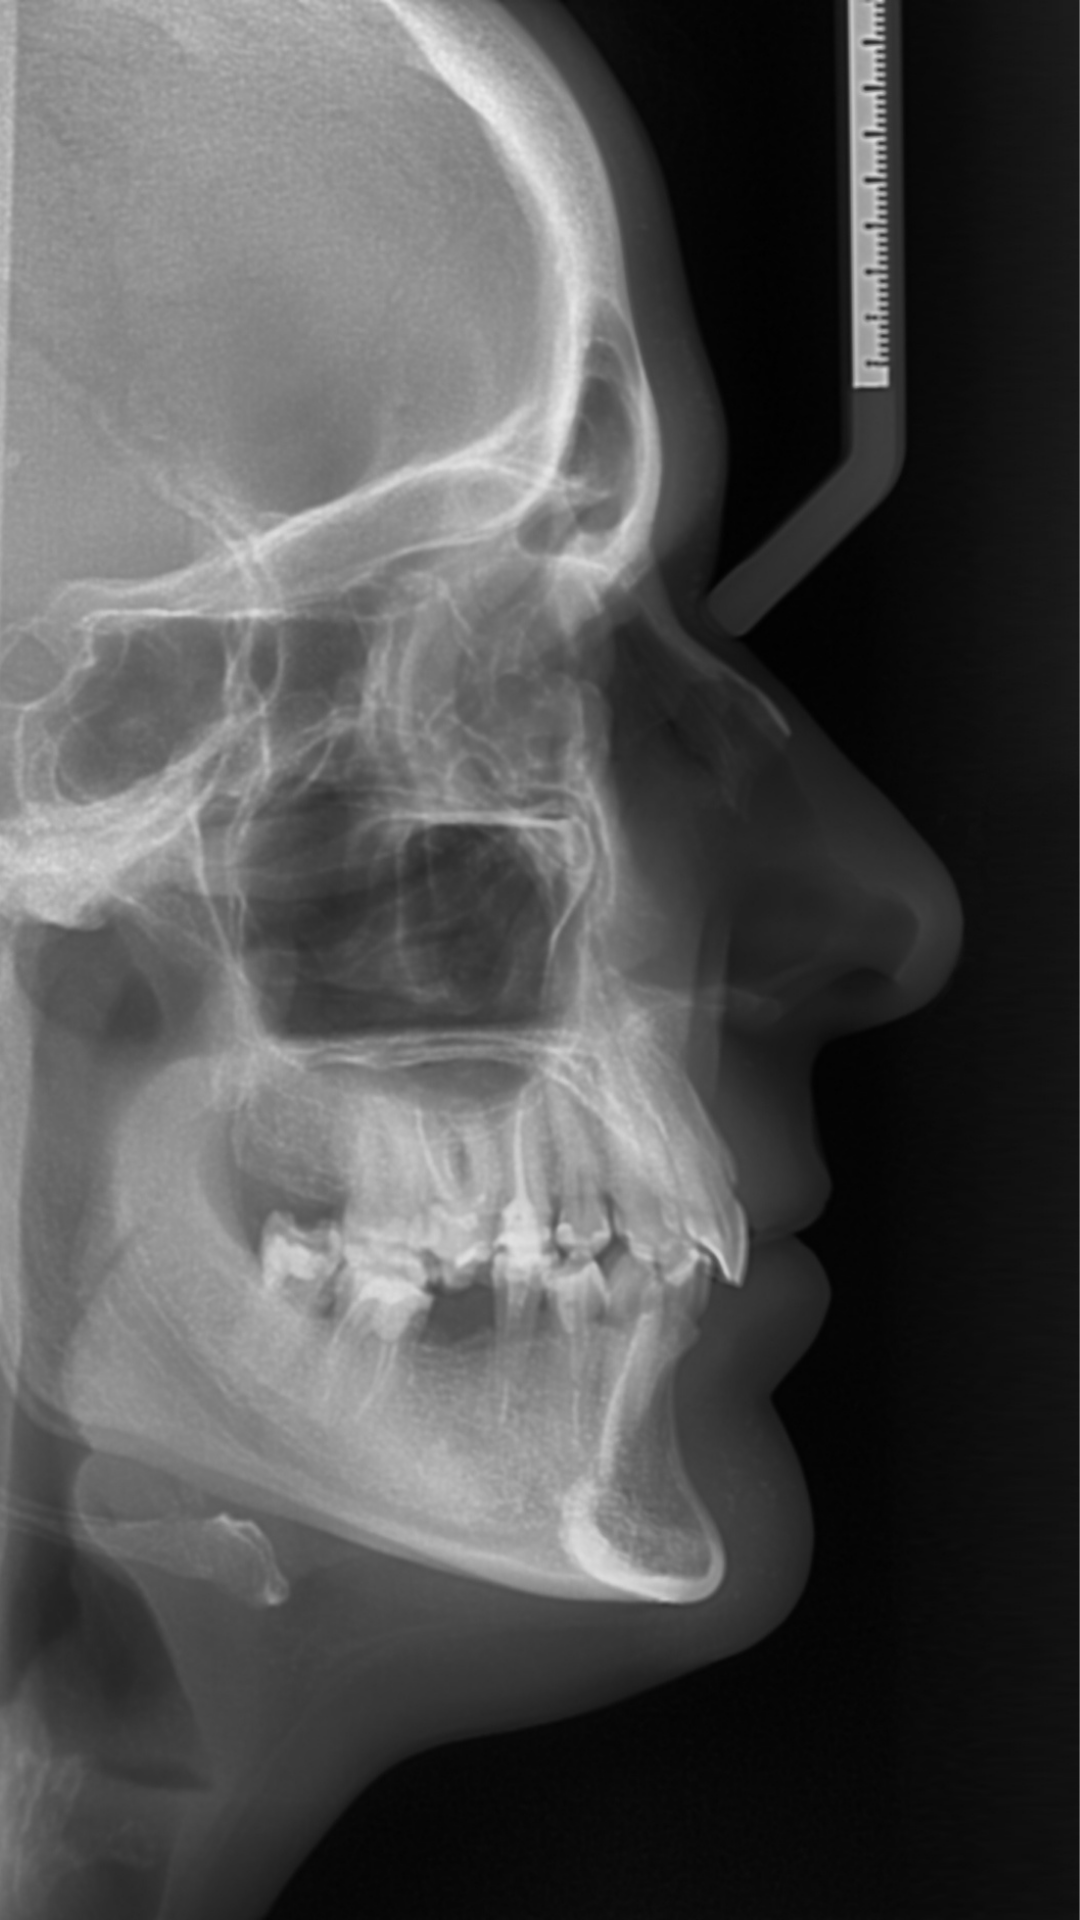

¿Buscas análisis biomecánicos avanzados? Nuestros estudios Orthokinética 2D te ofrecen evaluaciones detalladas para tratamientos personalizados.

¿Planeas un tratamiento de ortodoncia? Nuestros análisis ortodónticos 2D incluyen cefalometrías, modelos digitales y fotografías estandarizadas.